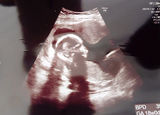

「すみません。病院がコロナ専用になるので、ここでの出産ができなくなりました」<略>定期検診に訪れた妊婦の女性(26)によると、医師から突然、切り出されたという。<略>医師からは、ほかの病院を複数紹介された。しかし、距離が遠かったり、費用が30万円ほど高くなったりするため、まだ転院先は決められていない。妊婦「急に転院迫られても…」都の3病院がコロナ専門に(朝日新聞デジタル) - Yahoo!ニュース

新型コロナウイルスの感染者数が急増した東京都は、都立と公社の計3病院を実質的な「コロナ専門病院」にすることを決めた。感染者の病床を確保するためだが、3病院では新型コロナ以外の診療や入院がほとんど停